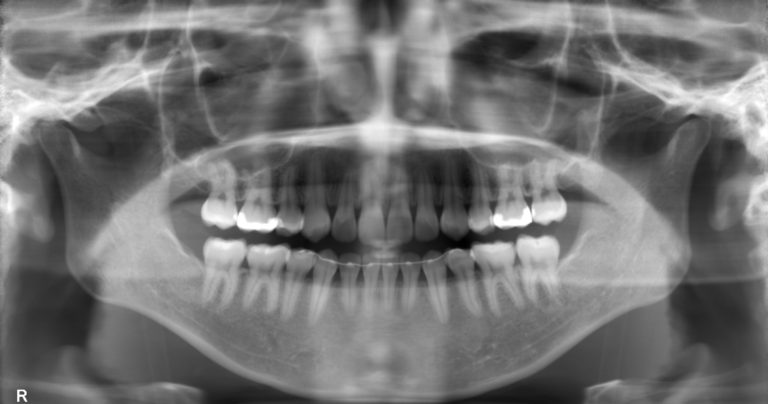

矯正治療における精密検査は、レントゲン・CT撮影、口腔内・顔面写真撮影、口腔内スキャンを行い、そこで得られた情報をもとに患者様一人ひとりにあった治療計画を立案するためにとても重要なステップです。旭川公園通り矯正歯科での精 … 続きを読む 矯正治療における精密検査の内容と目的